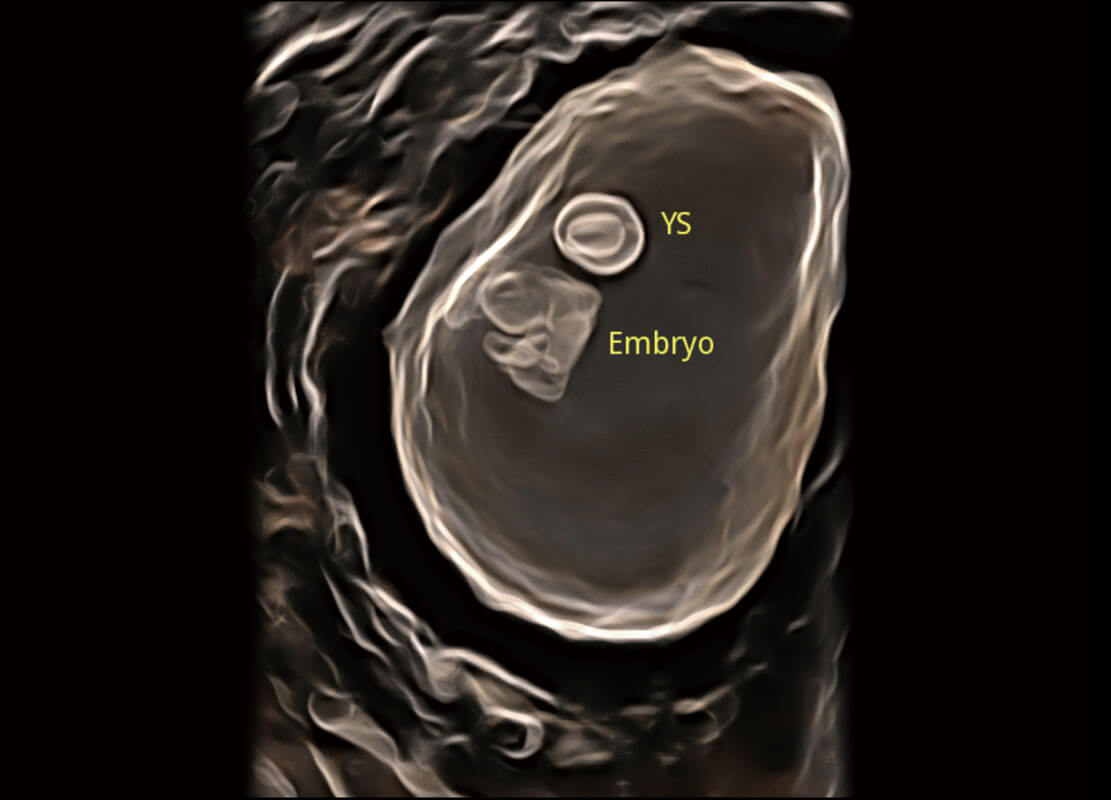

P60在胎儿早孕期超声筛查中为您带来优异的图像质量。

• 早孕-胎心

• 高分辨率容积成像-早孕胎儿

• 光影成像-孕囊